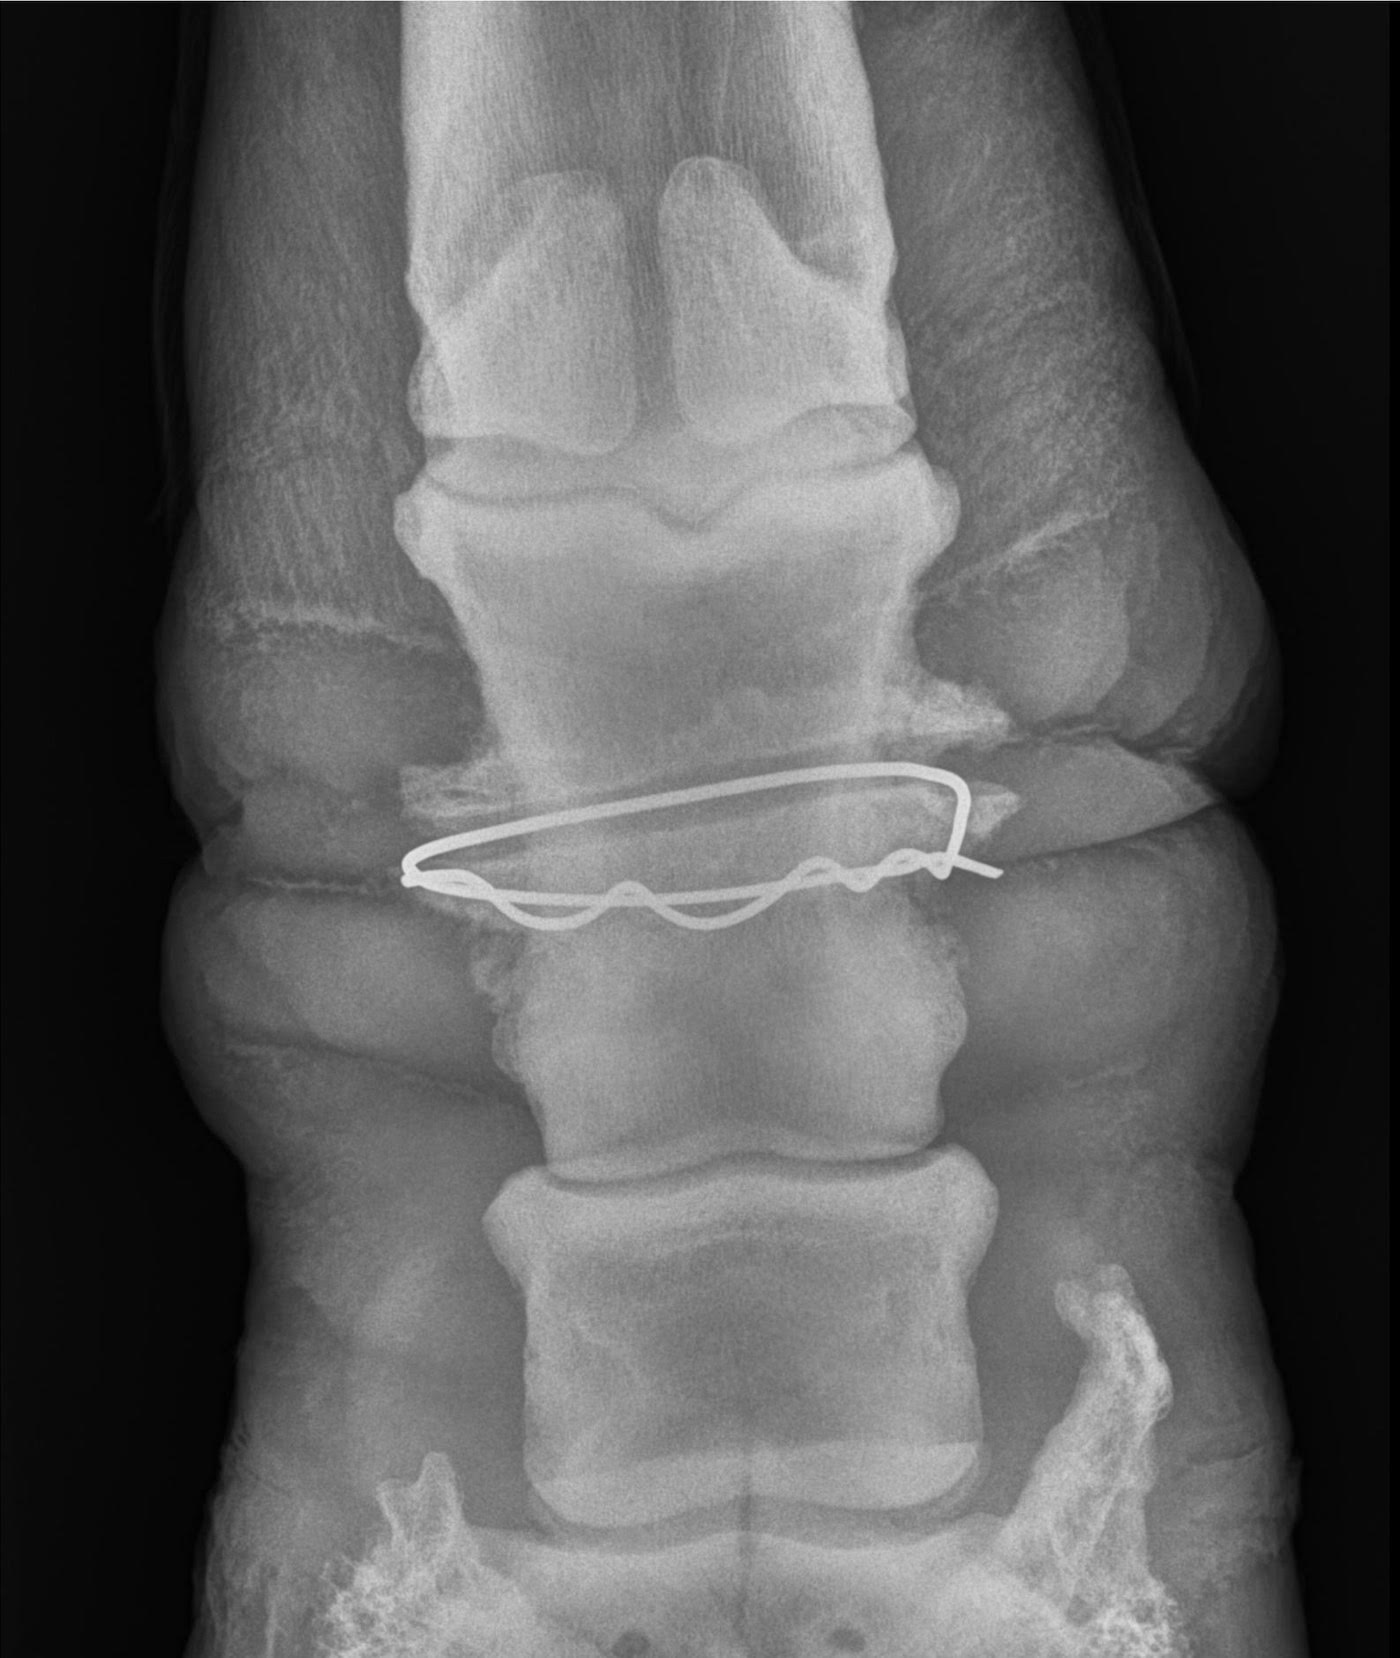

“The radiographs showed a metal wire had been wrapped around Zeke’s pastern bone, deeply embedded through the soft tissue and into the bone,” a spokesman for the rescue said.

Zeke was referred to Palm Beach Equine Clinic, where surgeon Weston Davies and Sidney Chanutin took more X-rays.

“The radiographs confirmed a metal object was circumferentially wrapped around the mid-pastern bone, embedded into the soft tissue and remodelled the bone itself,” Dr Chanutin said.

“ It was clear the wire had been embedded into Zeke’s pastern for months, based on the level of bone remodelling that had taken place,” the spokesman said.